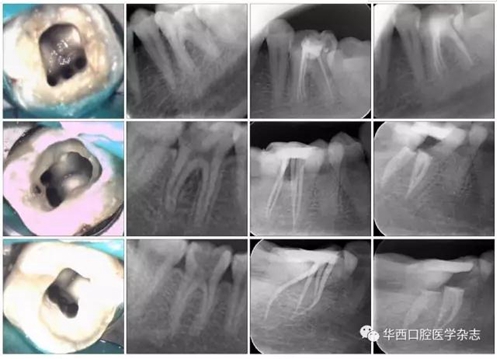

下頜第一恒磨牙MMC的三種可能解剖形態(tài)見圖4。

從上至下依次為“獨立”、“歧狀”和“融合”解剖型。

第一列:MMC 顯微鏡 ×16;

第二列:術(shù)前片;

第三列:試尖片;第四列:根充片。

圖4下頜第一恒磨牙MMC的三種可能解剖形態(tài)(Pomeranz分類)

在確定的17顆牙的近中三根管中,顯示“獨立”解剖(獨立根尖孔)的2顆(11.8%);顯示“歧狀”解剖(沒有單獨的根管口)6顆(35.3%);顯示“融合”解剖(具有單獨的根管口,最終在根尖方向融入到其中一個主根管)9顆(52.9%)(圖4)。在顯示“融合”解剖的9顆牙的近中三根管中,6顆融合到近中舌側(cè)根管,3顆融合到近中頰側(cè)根管。